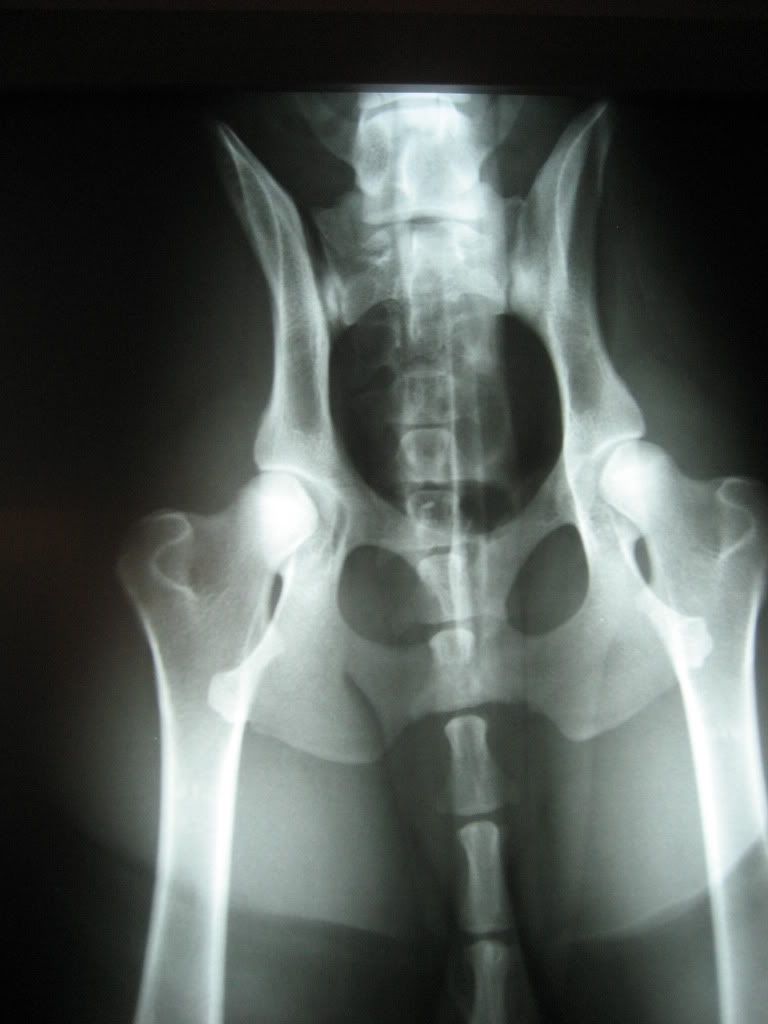

Dog Hip Xrays . in cats the reported incidence of hip dysplasia amongst breeds ranges from about 6% to 32%, the diagnosis is usually made. hip radiographs are taken with the dog in complete muscle relaxation, making deep sedation or anaesthesia mandatory. The pennhip method of evaluation is more accurate than the current standard in its ability to predict the onset of osteoarthritis (oa). pennhip is a multifaceted radiographic screening method for hip evaluation. pelvic radiographs in dogs are commonly obtained to assess a variety of disorders, most commonly hip dysplasia and fractures. The technique assesses the quality of the canine hip and quantitatively measures canine hip joint laxity. The ability to obtain high.

Dog X Ray Showing Canine Bilateral Hip Dysplasia. Ventral View Stock Photo Alamy Dog Hip Xrays in cats the reported incidence of hip dysplasia amongst breeds ranges from about 6% to 32%, the diagnosis is usually made. The pennhip method of evaluation is more accurate than the current standard in its ability to predict the onset of osteoarthritis (oa). The ability to obtain high. hip radiographs are taken with the dog in complete muscle. Dog Hip Xrays.

Xray of Dog Abdomen and Pelvis Stock Image Image of pelvis, spine 30749653 Dog Hip Xrays hip radiographs are taken with the dog in complete muscle relaxation, making deep sedation or anaesthesia mandatory. The pennhip method of evaluation is more accurate than the current standard in its ability to predict the onset of osteoarthritis (oa). in cats the reported incidence of hip dysplasia amongst breeds ranges from about 6% to 32%, the diagnosis is. Dog Hip Xrays.